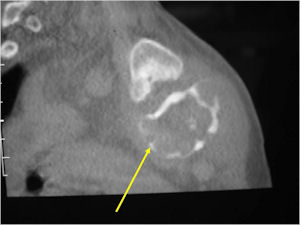

- Geographic, circumscribed lesion usually around 5cm in size.

- There may be expansion of bone, cortical thinning and cortical breakthrough. A soft tissue mass may accompany this lesion but the soft tissue component is usually contained by the periosteum.

- The periosteum remains intact around the soft tissue component. Might need a CT scan to detect the subtle calcification (Egg Shell Rim of Calcification) associated with an intact periosteal reaction

- The lesion may be entirely radiolucent but usually shows some degree of mineralization. Mineralization may appear stippled like cartilage but do not see chondroid pathologically. Mineralization is sometimes better detected on a CT scan rather than an x-ray.

- 4 cm to 6 cm in size

CT Scan:

- More useful for detecting mineralization and evaluating extent of bone destruction than plain X-ray